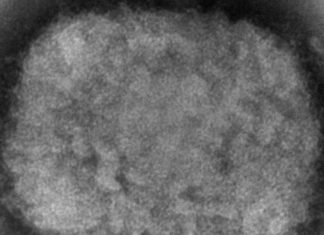

Detectado en Florida un posible caso de viruela del mono

Miami, EE.UU.- Las autoridades sanitarias de Florida detectaron un presunto caso de viruela del mono en el condado Broward, en el sur de este...

EEUU reporta primer caso de viruela símica en Massachusetts

Nueva York, EE.UU. — Massachusetts reportó el miércoles un raro caso de viruela símica en un hombre que viajó recientemente a Canadá, y los...